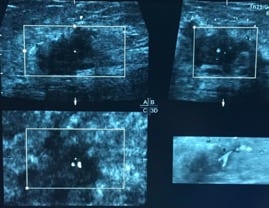

Ultrasonido de mama. El ultrasonido utiliza ondas de sonido para generar imágenes de las estructuras dentro del cuerpo. Se puede utilizar el ultrasonido para determinar si un bulto nuevo en la mama es una masa sólida o un quiste lleno de líquido.

• Cáncer de mama por ultrasonido